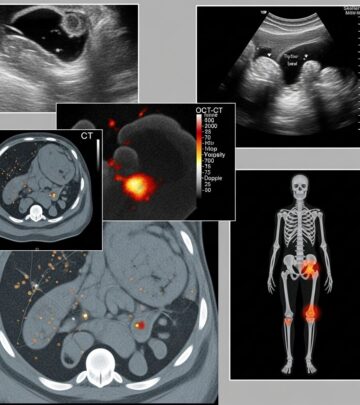

Radiographic Investigations In Melanoma: Essential Imaging Guide